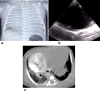

Cross-sectional imaging modalities like MRI and CT provide images of the chest which are easily understood by clinicians. However, these modalities may not always be available and are expensive. Lung ultrasonography (US) has therefore become an important tool in the hands of clinicians as an extension of the clinical exam, which has been underutilized by the radiologists. Reinforcement of the ALARA principle along with the dictum of "Image gently" have resulted in increased use of modalities which do not require radiation. Hence, ultrasound, which was earlier being used mainly to confirm the presence of pleural effusion as well as evaluate it and differentiate solid from cystic masses, is now being used to evaluate the lung as well. This review highlights the utility of ultrasound of the paediatric chest. It also describes the normal and abnormal appearances of the paediatric lung on ultrasound as well as the advantages and limitations of this modality.